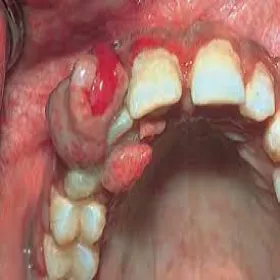

Nadziąślak ropotwórczy